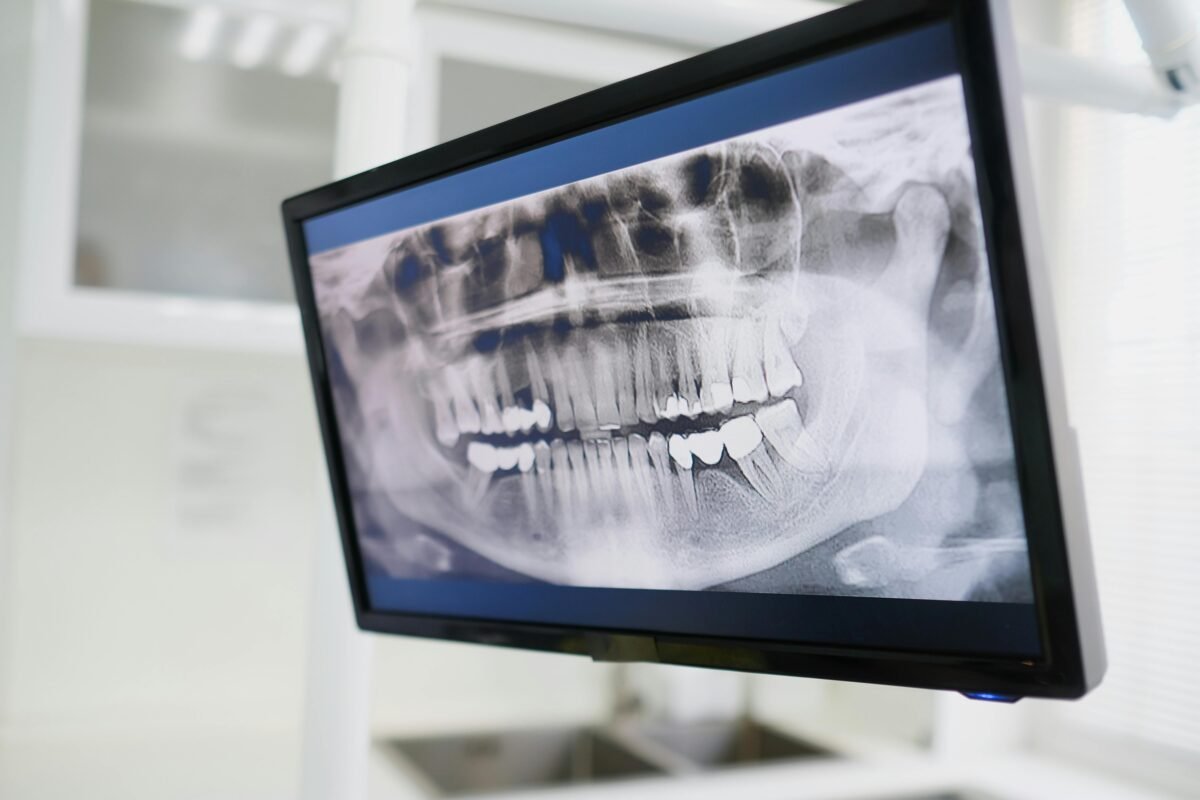

Diagnóstico Dental